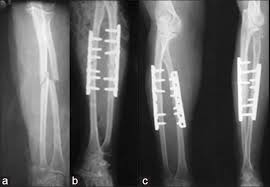

Adult Forearm Fractures

Your forearm is made up of two bones, the radius and ulna. In most cases of adult forearm fractures, both bones are broken.

Fractures of the forearm can occur near the wrist at the farthest (distal) end of the bone, in the middle of the forearm, or near the elbow at the top (proximal) end of the bone. This article focuses on fractures that occur in the middle segments of the radius and ulna. Fractures that involve the wrist or the elbow are discussed in separate articles. (See Related Topics list)

Forearm bones can break in several ways. The bone can crack just slightly, or can break into many pieces. The broken pieces of bone may line up straight or may be far out of place.

In some cases, the bone will break in such a way that bone fragments stick out through the skin or a wound penetrates down to the broken bone. This is called an open fracture and requires immediate medical attention because of the risk for infection.

Because of the strong force required to break the radius or ulna in the middle of the bone, it is more common for adults to break both bones during a forearm injury. When only one bone in the forearm is broken, it is typically the ulna — usually as a result of a direct blow to the outside of your arm when you have it raised in self defense.

Fractures of both the radius and ulna.

Treatment of broken bones follows one basic rule: the broken pieces must be put back into position and prevented from moving out of place until they are healed. Because the radius and ulna rely on each other for support, it is important that they are properly stabilized. If the bones are not accurately aligned during healing, it may result in future problems with wrist and elbow movement.

Most cases of adult forearm fractures require surgery to make sure the bones are stabilized and lined up for successful healing.